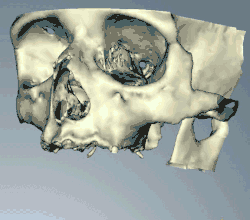

Pokud je potřeba přesnější plán nad rámec klinického úsudku, zhotoví zubní lékař před operací akrylové vodítko (tzv. stent), které slouží jako vodítko pro optimální umístění implantátu. Stále častěji se zubní lékaři rozhodují pro výpočetní tomografii čelistí a případných stávajících zubních náhrad a poté plánují operaci v CAD/CAM softwaru. Stent pak lze vyrobit pomocí stereolitografie po počítačovém naplánování z výpočetní tomografie. Použití tomografie ve složitých případech také pomáhá chirurgovi identifikovat a vyhnout se životně důležitým strukturám, jako je dolní alveolární nerv a sinus.[28][29]:s.1199

Úspěch nebo neúspěch implantace závisí na zdravotním stavu osoby, která je léčena, na lécích, které ovlivňují šanci na vhojení, a na stavu tkání v ústech. Posuzuje se také míra zatížení, která bude na implantát a fixací působit při běžné činnosti. Plánování polohy a počtu implantátů je klíčové pro dlouhodobé zdraví protézy, protože biomechanické síly vznikající při žvýkání mohou být značné. Poloha implantátů se určuje podle polohy a úhlu sousedních zubů, pomocí laboratorních simulací nebo pomocí výpočetní tomografie se simulacemi CAD/CAM a chirurgických pomůcek zvaných stenty. Předpokladem dlouhodobého úspěchu vhojení zubních implantátů je zdravá kost a dáseň. Protože obojí může po extrakci zubu atrofovat, jsou někdy nutné předprotetické zákroky, jako jsou sinus lift nebo dásňové štěpy, aby se znovu vytvořila ideální kost a dáseň.